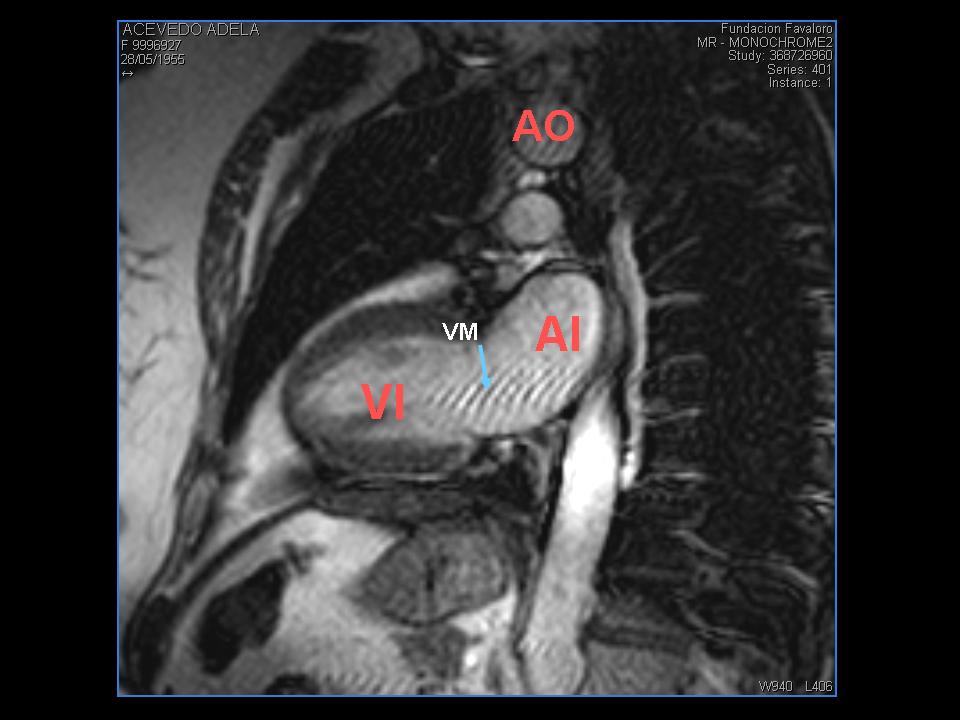

1-Localizador 2 camaras

Sobre una imagen axial en donde se observe el tabique interventricular se colocara el paquete de cortes paralelo al mismo,sobre el corazon izquierdo perpendicular a la situación de la valvula mitral atravesando el apex o punta del corazón,el producto de de esta programacion es la obtencion de una imagen mediosagital en donde se observa el corazon izquierdo o

dos camaras en donde:

se localiza la aurícula izquierda y ventrículo izquierdo,la válvula mitral la aorta y la arteria pulmonar sobre el eje largo,la calidad de la imagen es baja sirve para poder programar en base a esta el resto de los localizadores